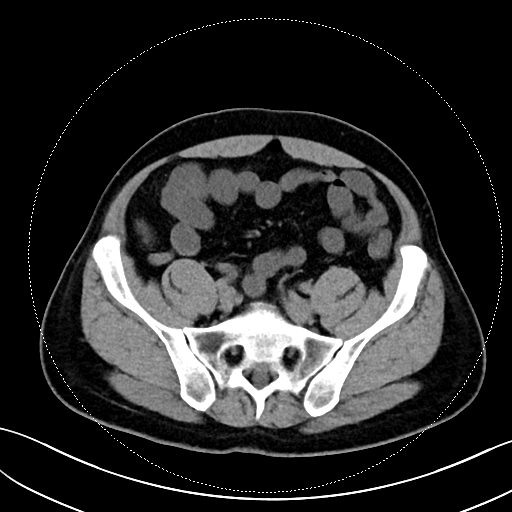

该患者的症状表现为钝痛,与进食、排便没有关联,也未出现发热、腹泻等伴随症状。在外院检查时,常规实验室检查如血常规、CRP、粪便钙卫蛋白均无异常,胃镜、结肠镜、胶囊内镜及超声内镜检查也未发现溃疡、肿瘤或克罗恩病的迹象。转诊至我院后,马师洋副教授团队另辟蹊径,对患者的腹部 CT 进行了细致入微的 “像素级” 阅片,并通过三维重建分析,敏锐地捕捉到阑尾根部呈现 “折角样” 扭曲,管腔局部狭窄且粘膜皱襞紊乱,虽无典型阑尾炎的周围脂肪条索、粪石等征象,但这一发现与患者的疼痛定位高度吻合,初步判断为非梗阻性阑尾功能障碍。

关键影像图片